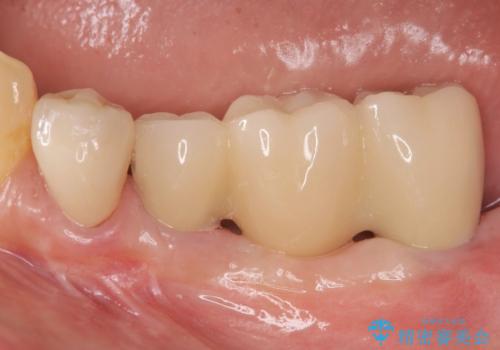

過大な咬合力で破折した奥歯 インプラント治療で咬合機能の回復